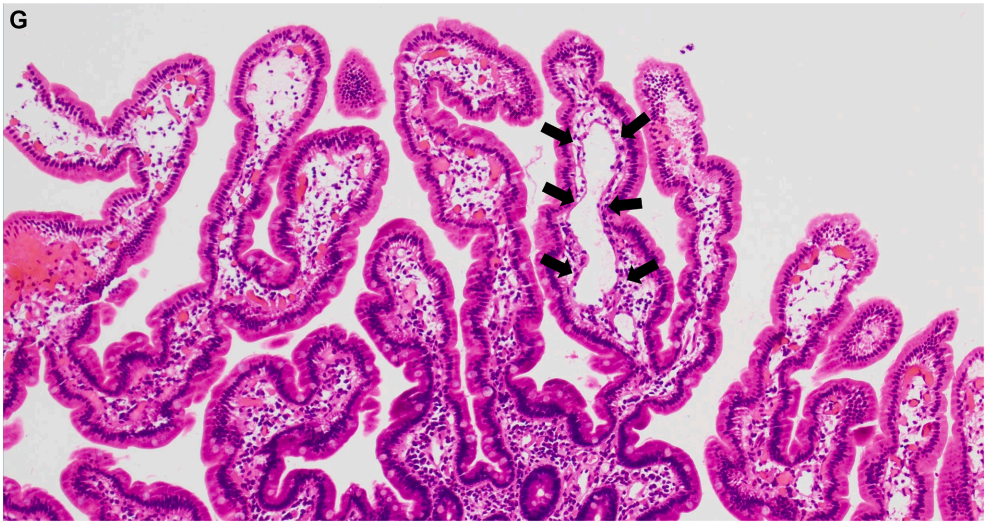

鉴于患者存在持续低白蛋白血症,且未见明确肾脏、肝脏及营养相关病因,遂行进一步检查。粪便α-1抗胰蛋白酶(A1AT)升高至356mg/dL,A1AT清除率升高至171mL/24h。胸部CT示左侧胸壁内多发血管扩张,提示可能存在血管异常(图A)。腹部磁共振成像(MRI)发现2个亚厘米级血管瘤,分别位于肝右后下缘尖端及肝右叶下段(图B、C)。

A1AT清除率检测是诊断PLE的金标准,结果证实患者存在异常肠道蛋白丢失。PLE的鉴别诊断包括胃肠道黏膜损伤、黏膜通透性增加及淋巴管阻塞。推进式小肠镜检查显示乳糜管弥漫性扩张,符合肠淋巴管扩张症表现。乳糜泻相关血清学检测阴性,小肠活检标本未见炎性浸润、上皮内淋巴细胞或绒毛异常,但可见淋巴管扩张(图G,黑色箭头)。